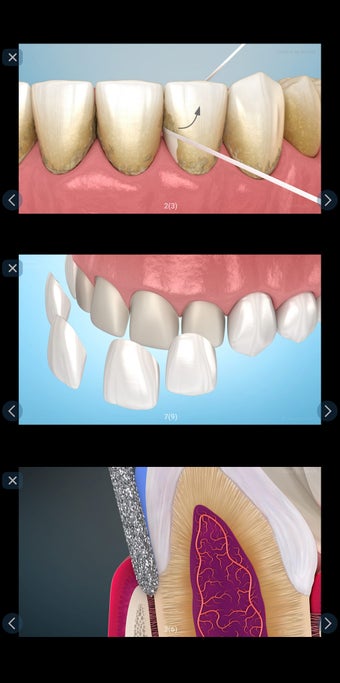

إذا كنت متخصصًا في طب الأسنان أو مريضًا، فقد تساعدك هذه الأداة في تعلم علاجات الأسنان.

تم إنشاء هذا التطبيق بواسطة أليكس ميت للأطباء الأسنان وطلاب طب الأسنان والمرضى. كما يمكن استخدامه أيضًا من قبل المهنيين الطبيين الآخرين.

يستند التطبيق على مبدأ عرض الشرائح. يحتوي كل موضوع على 3-9 صور. يمكن عرض صور أي موضوع في أي وقت.